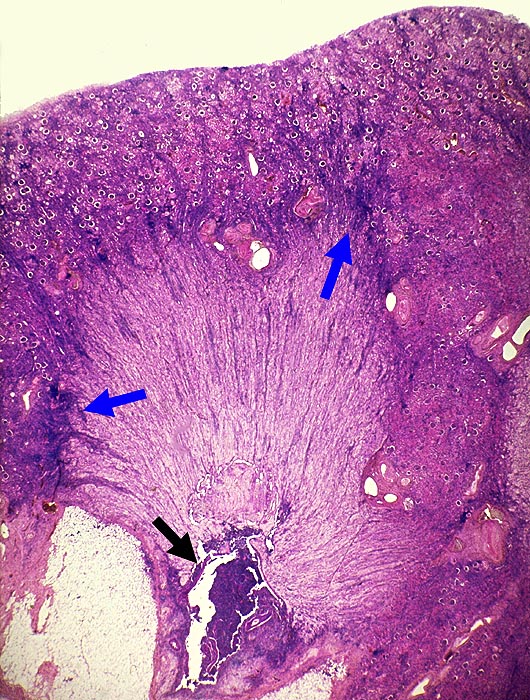

Papillennekrosen bei Analgetikanephropathie

Papillennekrose. Die Papillenspitze ist abgestossen. Das gesamte Nierenmark ist praktisch nekrotisch. Innerhalb der Nekrose bilden sich schlitzförmige Lücken, die in einzelnen Fällen auch radiologisch darstellbar sind. An der Grenze zur Rinde besteht ein herdförmig akzentuiertes Infiltrat. Das gesamte Nierenrindengewebe ist leicht geschrumpft. Die Glomeruli sind erhalten.